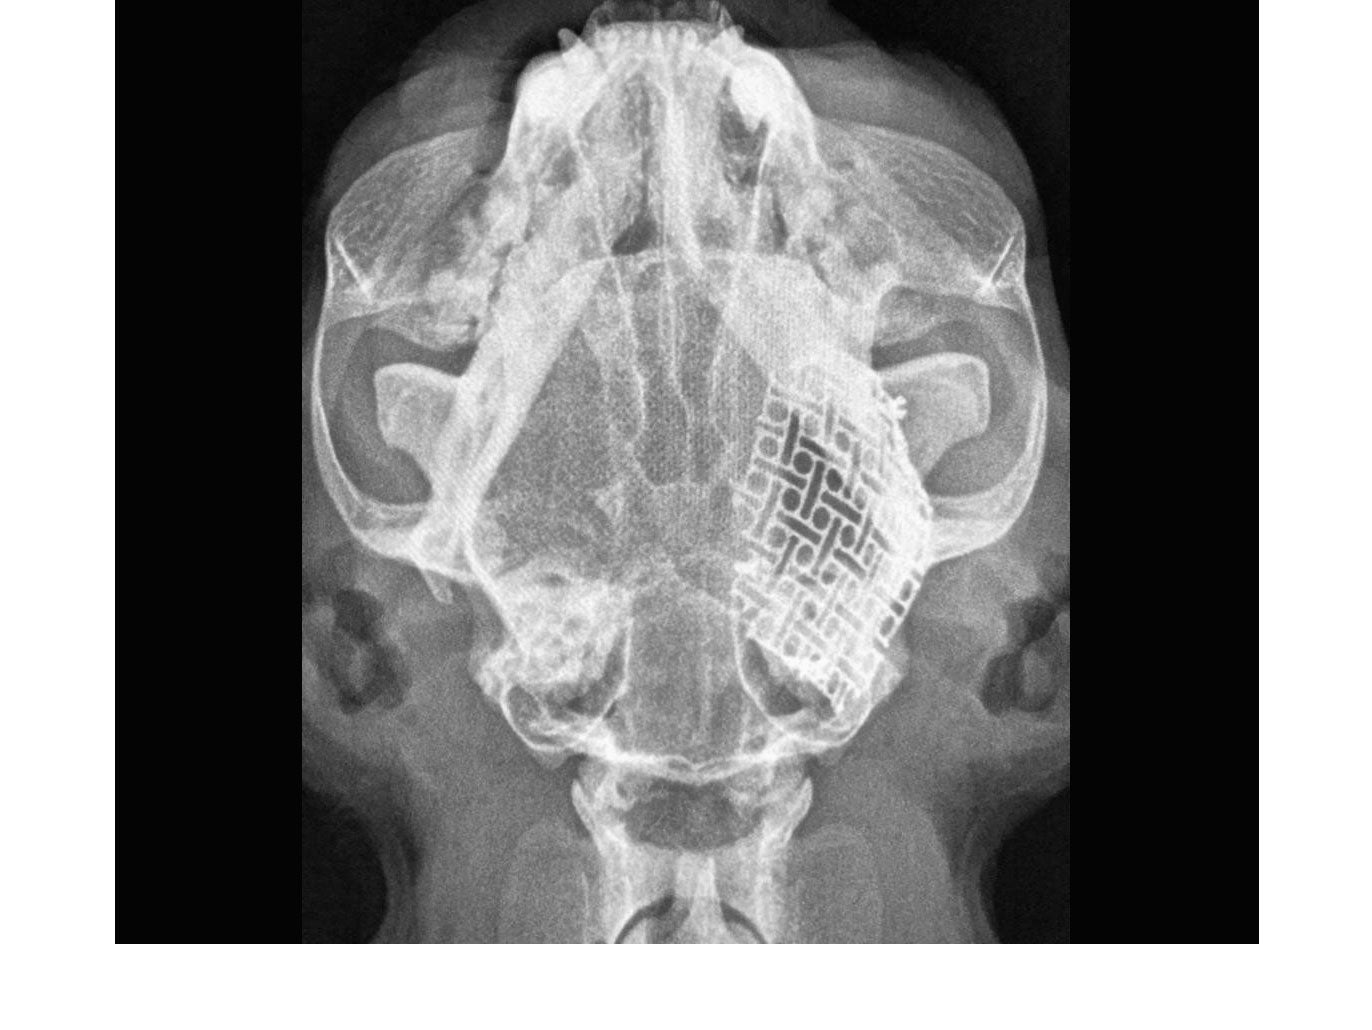

neuromesh™ is a cuttable, medical grade titanium cranioplasty solution which can be moulded to match the skull shape of each individual patient, regardless of their size.

neuromesh™ provides for the ability of "on site" engineering, allowing the surgeon more versatility when faced with repairing skull defects or maxillofacial reconstruction. It can be used to maintain the aesthetic appearance of the patient, provide for structural support and protect the brain when surgery requires the removal of excessive amounts of skull. It saves time and opens the door to more advanced cranioplasty procedures.

Cuttable and easy to contour makes neuromesh™ a perfect solution for the reconstruction of cranial defects. Easily adaptable to contour to the anatomical curvature of craniums all varying shapes and sizes and uses low-profile titanium screws for fixation.